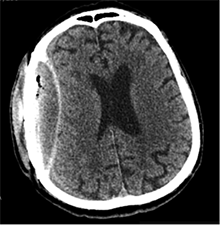

Po 2 savaičių pacientas rastas parkritęs kieme. Buvo matyti kraujuojanti žaizda. Pacientas pakartotinai hospitalizuotas į Neurochirurgijos skyrių. Atlikus GKT, nustatyta 25 mm storio hipodencinė juosta virš dešiniojo smegenų pusrutulio ir 8 mm vidurinių smegenų struktūrų dislokacija (VSD) į kairę (3 pav.). Įtariant lėtinę SDH dešinėje pusėje, pacientas reoperuotas, atliekant rekraniotomiją. Operacijos metu ant kietojo smegenų dangalo (KSD) rasta fibrino, jis pašalintas. Pravėrus KSD, rastas drumstas turinys, nesant aiškių pūlių, ir stora kapsulė. Gausiai praplauta šiltu fiziologiniu tirpalu subduraliai. Kaulinis lopas grąžintas (4 pav.). Po operacijos pacientas pradėjo skųstis stipriu galvos skausmu, tapo vangus. GKT pakartota. Įtarta empiema, nustatyti oro tarpai subduraliai, galvos smegenų VSD – 6 mm. Praėjus 12 dienų po antros operacijos, pacientas operuotas pakartotinai. Operacijos metu atlikta rekraniotomija. Epiduriniame ir subduriniame tarpuose rasta pūlių ir fibrino. Pūliai ir fibrinas pašalinti, paimtas bakteriologinis pasėlis. Žaizda gausiai praplauta šiltu fiziologiniu tirpalu. Kaulinis lopas negrąžintas, minkštieji audiniai susiūti (5 pav.). Po operacijos paciento būklė stabilizavosi. Bakteriologiniame pasėlyje negausiai užaugo E. coli, jautri ampicilinui. Nesant teigiamo efekto gydant ampicilinu, dar 2 savaites pacientui skirta gentamicino. Praėjus 3 savaitėms po trečios operacijos, pacientas perkeltas į slaugos ligoninę palaikomojo gydymo.

3 pav. Prieš antrąją operaciją (25 mm storio hipodencinė juosta virš dešiniojo smegenų pusrutulio, esant 8 mm dislokacijai į kairę; įtarta lėtinė SDH dešinėje)